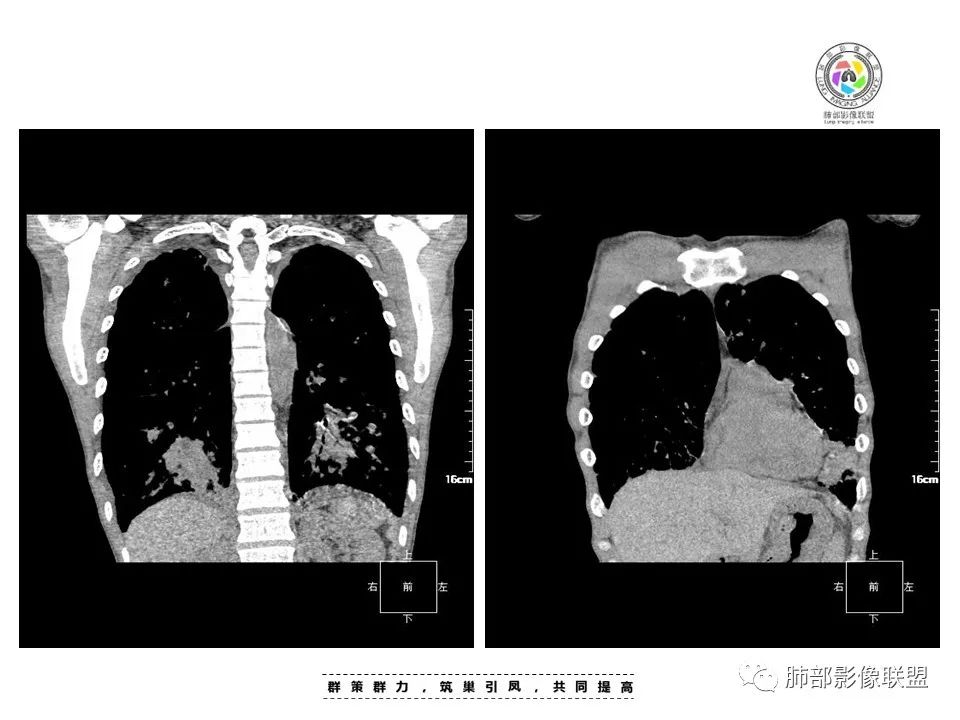

中年男性,发热、全身散在暗紫色丘疹,查CD4+T细胞64个/ul,临床信息提示AIDS并发卡波西肉瘤;CT提示双肺多发实性结节影及毛玻璃结节,部分呈点晕征,右上肺大姐姐边缘膨隆、分叶伴晕;双下肺结节沿支气管血管束分布,中轴间质增粗,部分支气管堵塞,叶间裂结节状增厚,部分结节胸膜下分布,可疑局部小叶间隔增厚,肺部病变呈淋巴分布特点,结合临床肺部病变考虑肺卡波西肉瘤,鉴别淋巴瘤。

2.本例双肺小叶间隔增厚明显,多发结节影及片状实性密度影,沿血管支气管束分布为主,两侧较为对称,病灶多环以磨玻璃晕,边界不清。

双侧胸腔少量积液。双肺门及纵隔未见明确肿大淋巴结,纵隔结构间隙模糊。

1.结节型:两肺沿支气管血管束分布的结节影,呈火焰状或星芒状、挂果征,局部周围出血磨玻璃影(肺泡出血或水肿)。

2.支气管血管束增粗型:

肺门周围支气管壁呈“套袖样”改变。

斑片渗出影,部分融合呈“火焰样”,同时有火焰样结节,小叶间隔增厚等表现。

还可以有纵隔及腋下淋巴结增大,胸腔积液等表现。